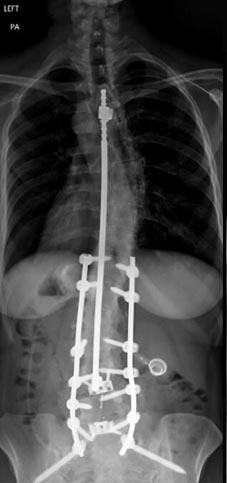

46 year old woman who previously had Harrington rod spinal fusion from T4 to L3 for idiopathic adolescent scoliosis who presents with back pain and left leg weakness from severe lumbar stenosis distal to her previous fusion.

3 months postop, patient is pain free and weakness completely resolved. She is able to stand upright without pain and improved posture.